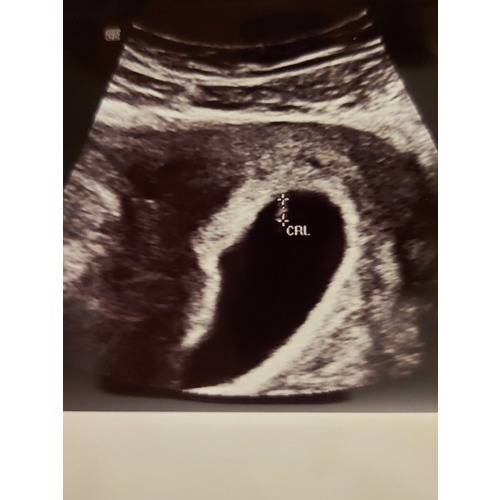

Gelukkig dat het goedgekomen met jouw zoontje🙌 Ik heb 4 december clearblue test gemaakt, er stond dat ik 3+ weken zwanger ben. Ik snap helemaal niet waarom de tweede embryo veel kleiner en heeft nog geen hartfunctie...

Wij krijgen vandaag de tweede echo en ik hoop dat we ook wat meer info krijgen... Ik vind het super spannend, want de eerste dag van mijn laatse cyclus was 1 november. 4 december er stond "3+ weken zwanger" op de zwangerschapstest (wat betekent 5+ weken). 20 december heb ik bloedverlies gekregen en de eerste echo...

Het wordt echt een wonder, als er een kleine gezonde embryo is. 1,5 jaar geleden wij hebben ons zoontje na bijna 24 weken zwangerchap verloren(hartafwijking) en nu dit miskraam... Echt balen...

Wij gaan nog een echo over een week maken. Maar de verloskundigen denkt, dat die tweede embryo is gestopt met groeien. En dat ik nog meer bloedverlies kan verwachten... Zo rare gevoelens... Zij heeft mij ook gevraagd of ik een afspraak voor curettage wil. Wij besloten nog een week afwachten. Als het hartje gaat niet kloppen of als ik meer bloedverlies niet ga krijgen, dan gaan we die afspraak maken voor een operatie... Ik vind het zo bijzonder, dat ik van een tweeling zwanger ben/was...jammer dat het niet zo perfect is gegaan💔